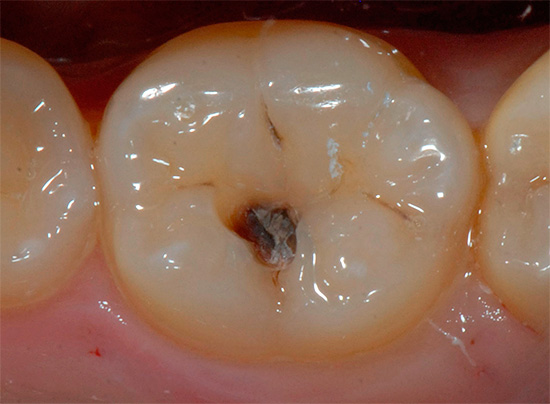

Una cavità dentale viene sondata da un dentista usando una sonda, uno strumento speciale puntato all'estremità. In caso di ammorbidimento del tessuto dentale, la sonda si guasta o si blocca. In questo caso, è possibile una sensazione di dolore.

Se la carie dentaria ha raggiunto la dentina del dente, significa che hai già perso il momento in cui il trattamento dei cambiamenti patologici potrebbe essere eseguito senza l'uso di un trapano. In questa fase, una visita da un medico di solito non è completa senza perforare i denti e installare otturazioni.

- Elaborazione del dente da tessuti cariati e infetti (usando un trapano);